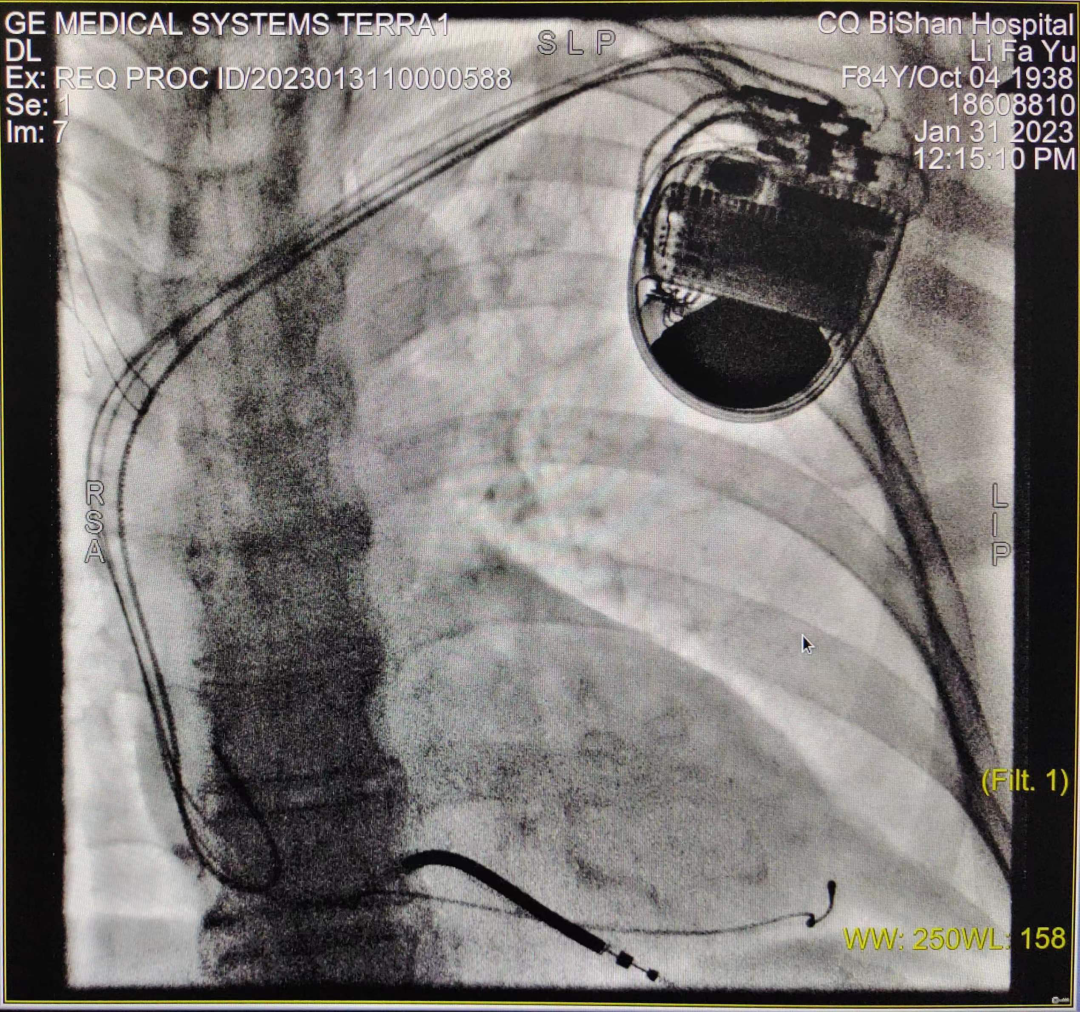

CRT-D植入術(shù)進(jìn)行中

于長青主任高度重視,結(jié)合患者既往病史、治療史,先后多次組織科室團(tuán)隊(duì)及醫(yī)院MDT團(tuán)隊(duì)討論,并報請醫(yī)務(wù)科批示,最終決定給該患者安置三腔起搏器,實(shí)施雙心室同步起搏的心臟再同步化治療,改善患者的心力衰竭癥狀。科室起搏電生理團(tuán)隊(duì)經(jīng)過充分的術(shù)前準(zhǔn)備,于1月31日成功為患者實(shí)施CRT-D介入手術(shù),手術(shù)過程順利,患者無任何不適,術(shù)后5天即安全出院。術(shù)后心電圖提示:竇性心律,雙心室起搏心律,QRS寬度120-130ms,患者勞累氣促癥狀較前明顯改善。